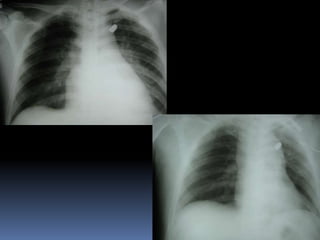

HEMOTORAX

HEMOTORAX MASIVO

ACUMULACION

RAPIDA DE MAS

DE 1,500CC

SHOCK

AUSENCIA DE M.V

PERCUSION : MATE

opacificación de un hemitórax

Sin rpta reposición volumen

Deterioro

Hemotorax 1500 cc o más toracotomía

200ml/h en 4h

500ml en 1 h

< 1000cc 100ml/h en 6-8h

cesa la hemorragia se hospitaliza

Hemoneumotórax